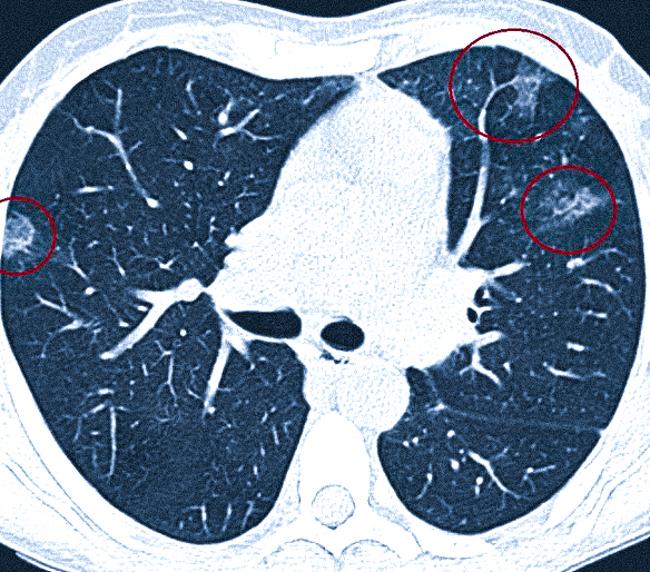

Ключевые исследования включают получение изображений легких с помощью рентгенографии и компьютерной томографии (КТ). Для характерного интерстициального заболевания легких присущи мелкие узелковые образования, сетчатые структуры и общая тень. Высокое разрешение КТ помогает в определении конкретного типа интерстициального заболевания учётом характера и распределения легочных теней на снимках.

Видно ли пневмофиброз на КТ легких

КТ считается золотым стандартом для диагностики пневмофиброза. Это исследование с высокой вероятностью может обнаружить рубцовые изменения, определить точное местоположение, размеры, форму и другие характеристики. КТ основано на рентгеновском излучении для создания черно-белых изображений, на которых области различной плотности отображаются по интенсивности затенения.

КТ признаки пневмофиброзных изменений в легких

Компьютерная томография позволяет увидеть мельчайшие рубцы, возникающие на месте воспалительных очагов после их заживления. Эти образования могут возникать в области хирургических вмешательств.

На определенном этапе фиброза наблюдаются изменения и визуальные дефекты в виде «матового стекла» в местах увеличенной плотности легочной ткани. Эти участки выглядят светлее по сравнению с нормальными участками паренхимы, так как они мягче пропускают рентгеновские лучи.

При обширном распространении фиброза характерна картина «сотового легкого» — множество кистозных образований, находящихся в несколько рядов. Внутри таких полостей содержится воздух, а стенки толще, чем обычные межальвеолярные перегородки. В ходе гистологического анализа также обнаруживается преобладание соединительной ткани.

Очаги изменения легочной ткани по типу “матового стекла”